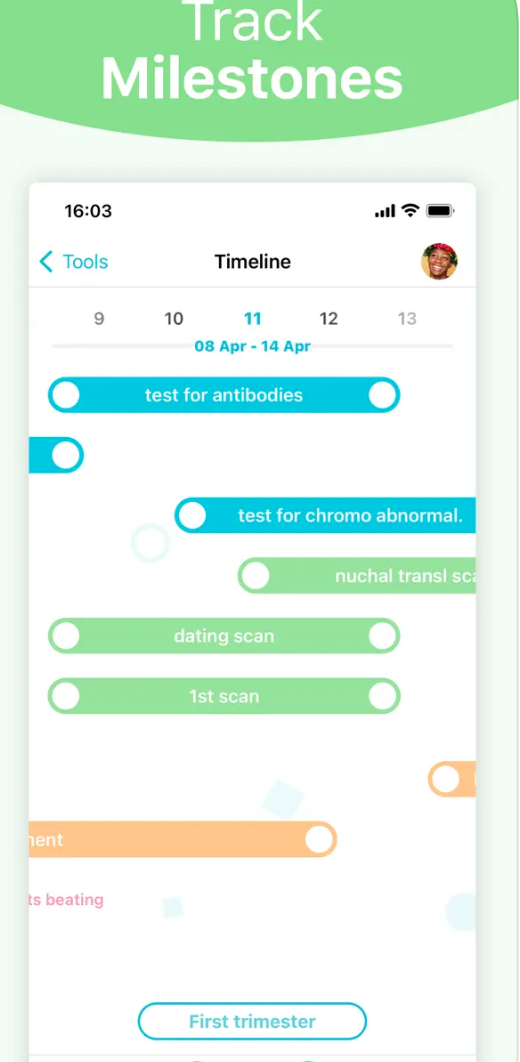

Pregnancy+

Jak název napovídá, aplikace Pregnancy+ je určená těm, kterým se již podařilo počít potomka. Pregnancy+ vás provede vaším těhotenstvím od začátku až do konce, bude vám neustále podávat související informace, zajímavosti a tipy. Najdete zde užitečné články, zajímavé ilustrace a 3D modely a spoustu dalšího.